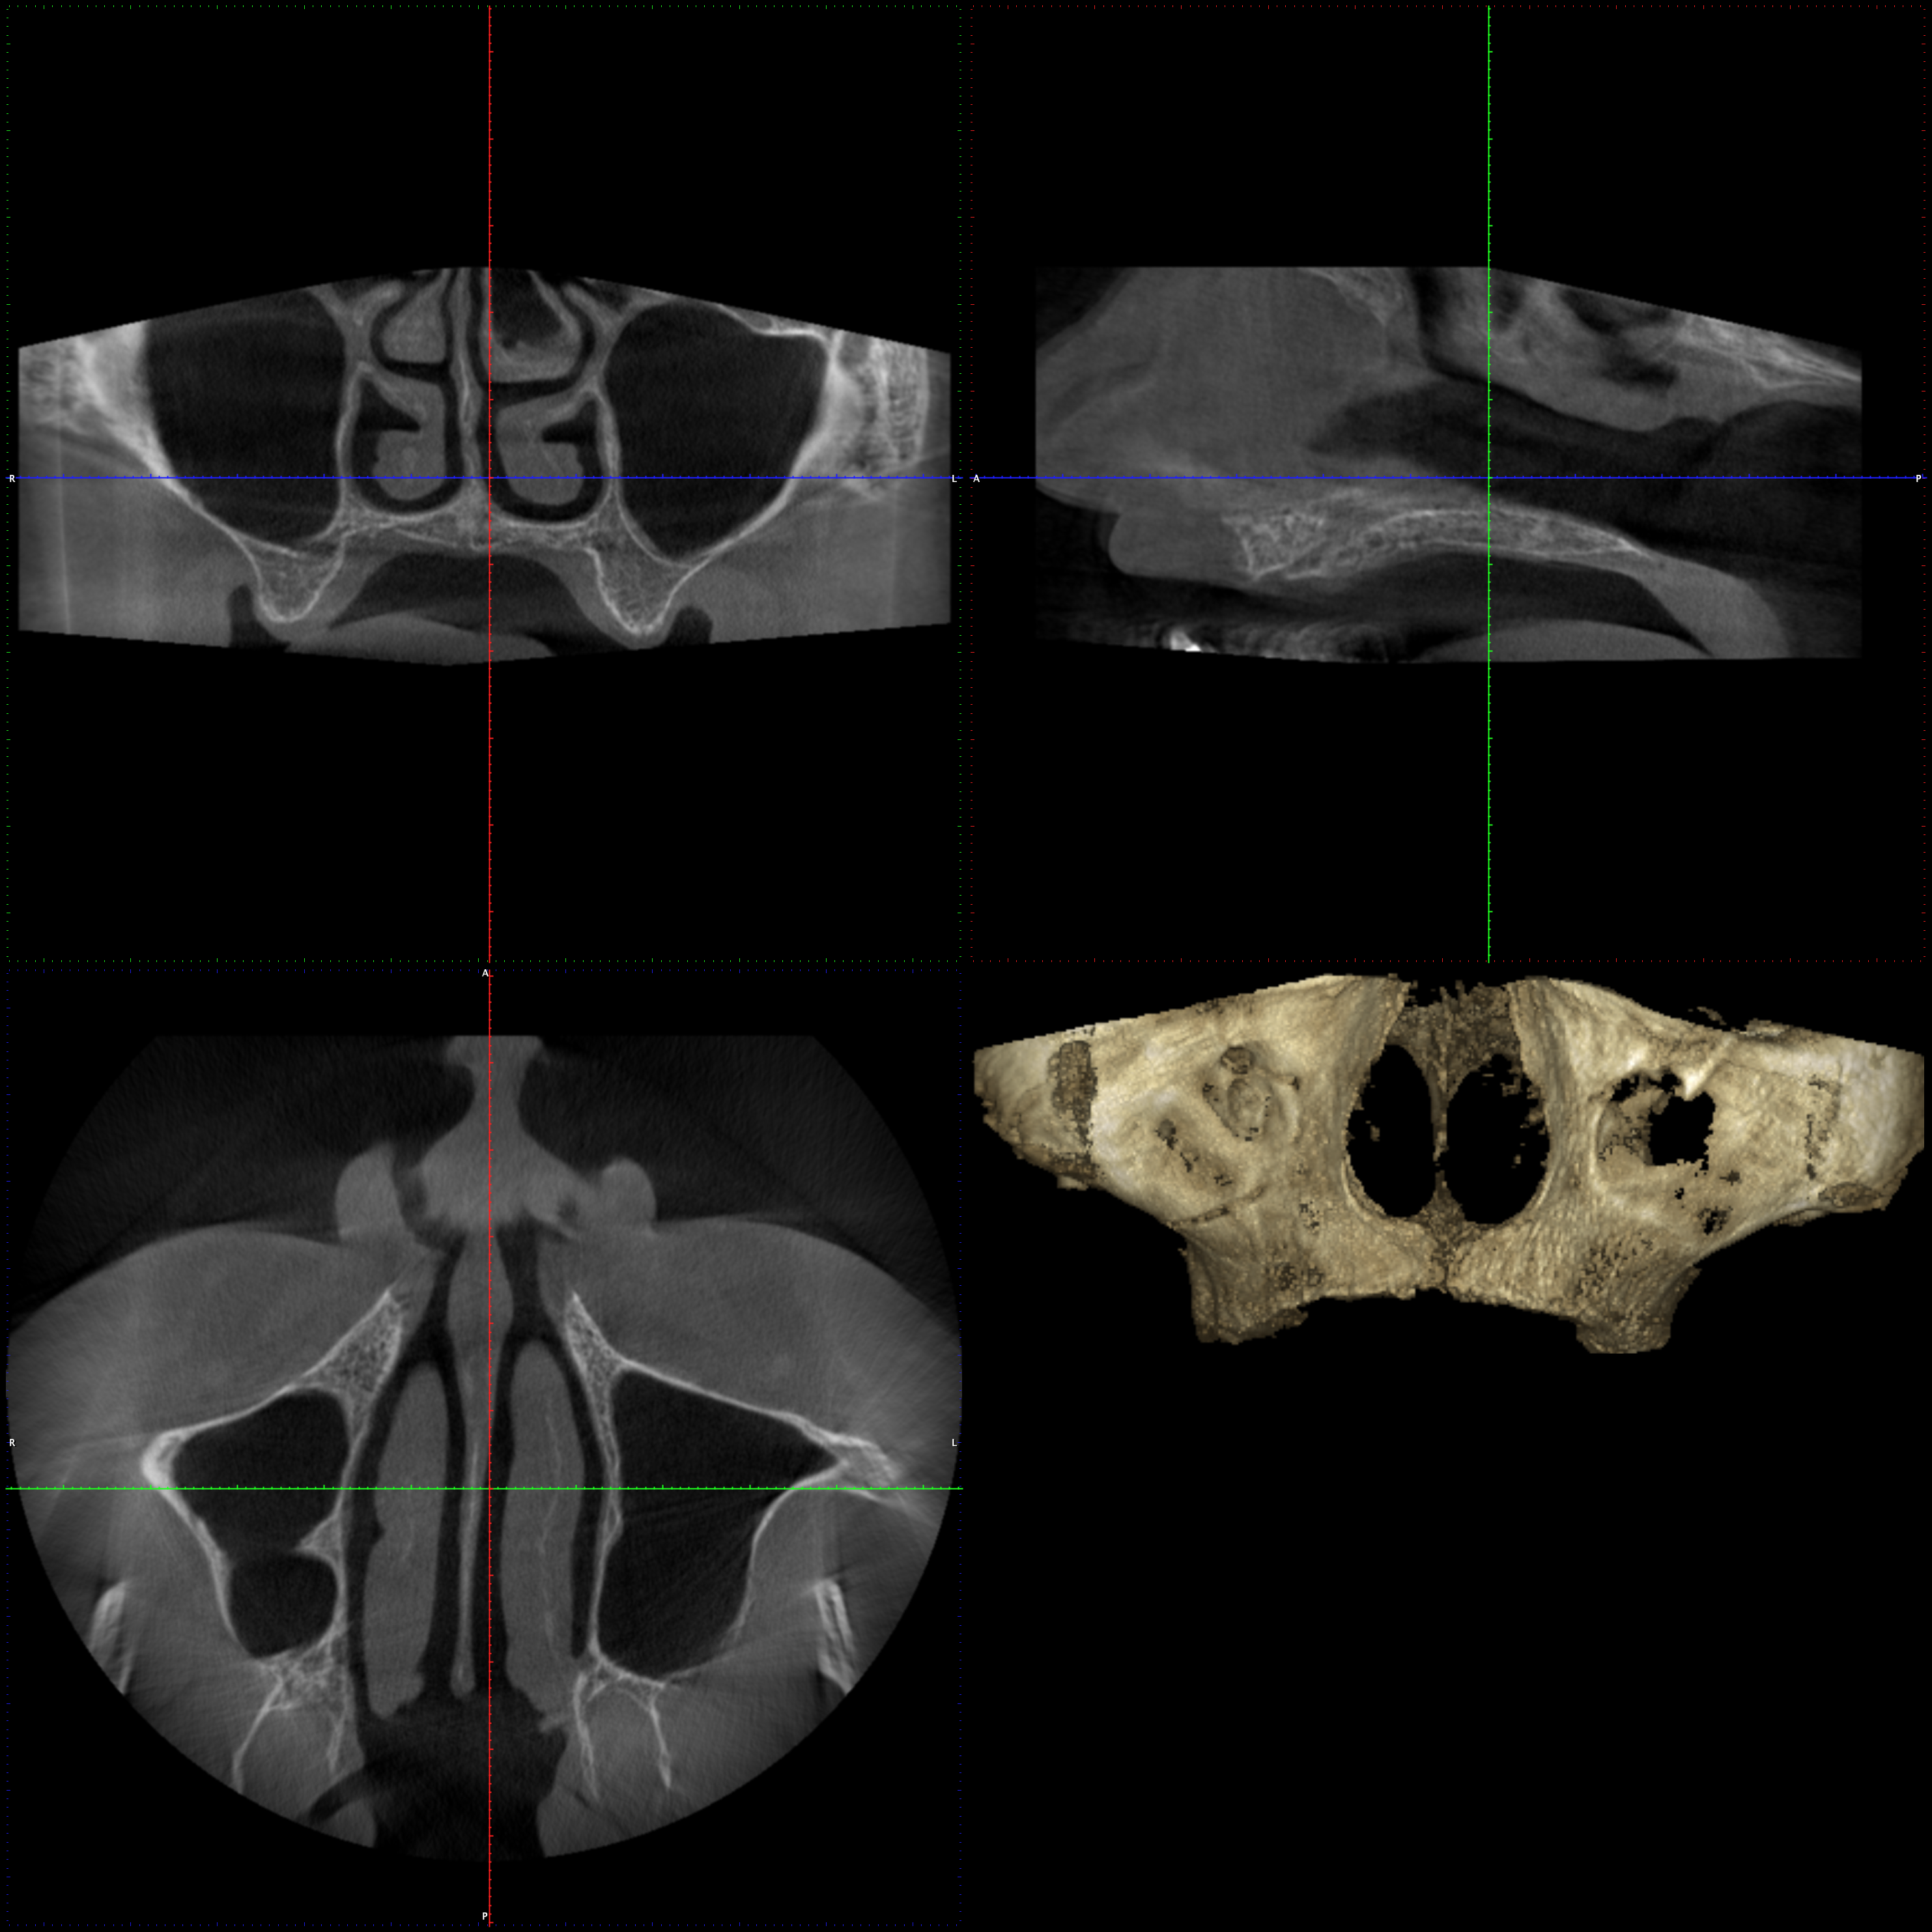

En PROTAC conseguimos una combinación ideal de calidad de imagen y usabilidad de alto nivel, ya que disponemos de una unidad CBCT(Cone Beam Computed Tomography) de última generación que supone un extraordinario avance en la evolución del procesamiento de imágenes de haz cónico, obteniendo una calidad de imagen optimizada, reduciendo los artefactos y garantizando imágenes de mayor contraste, para conseguir así satisfacer las necesidades del exigente procesamiento de imágenes maxilofaciales en todos los entornos clínicos. Nuestro innovador software Planmeca Romexis® ofrece herramientas especialmente diseñadas para especialistas en implantología, endodoncia, periodoncia, prostodoncia, ortodoncia, cirugía maxilofacial y otorrinolaringología.

Nuestra unidad de escáner y radiografía dental y nuestro software de procesamiento de imágenes brinda una combinación innovadora de imágenes 2D y 3D que le ofrecen una visión más completa para conocer con mayor exactitud las necesidades de sus pacientes.

Unidad CBCT de última generación con una calidad de imagen optimizada.

Software con herramientas especializadas para implantología, endodoncia, periodoncia, prostodoncia, ortodoncia, cirugía maxilofacial y otorrinolaringología.

Imágenes 2D y 3D más completas para conocer con mayor exactitud las necesidades de sus pacientes.